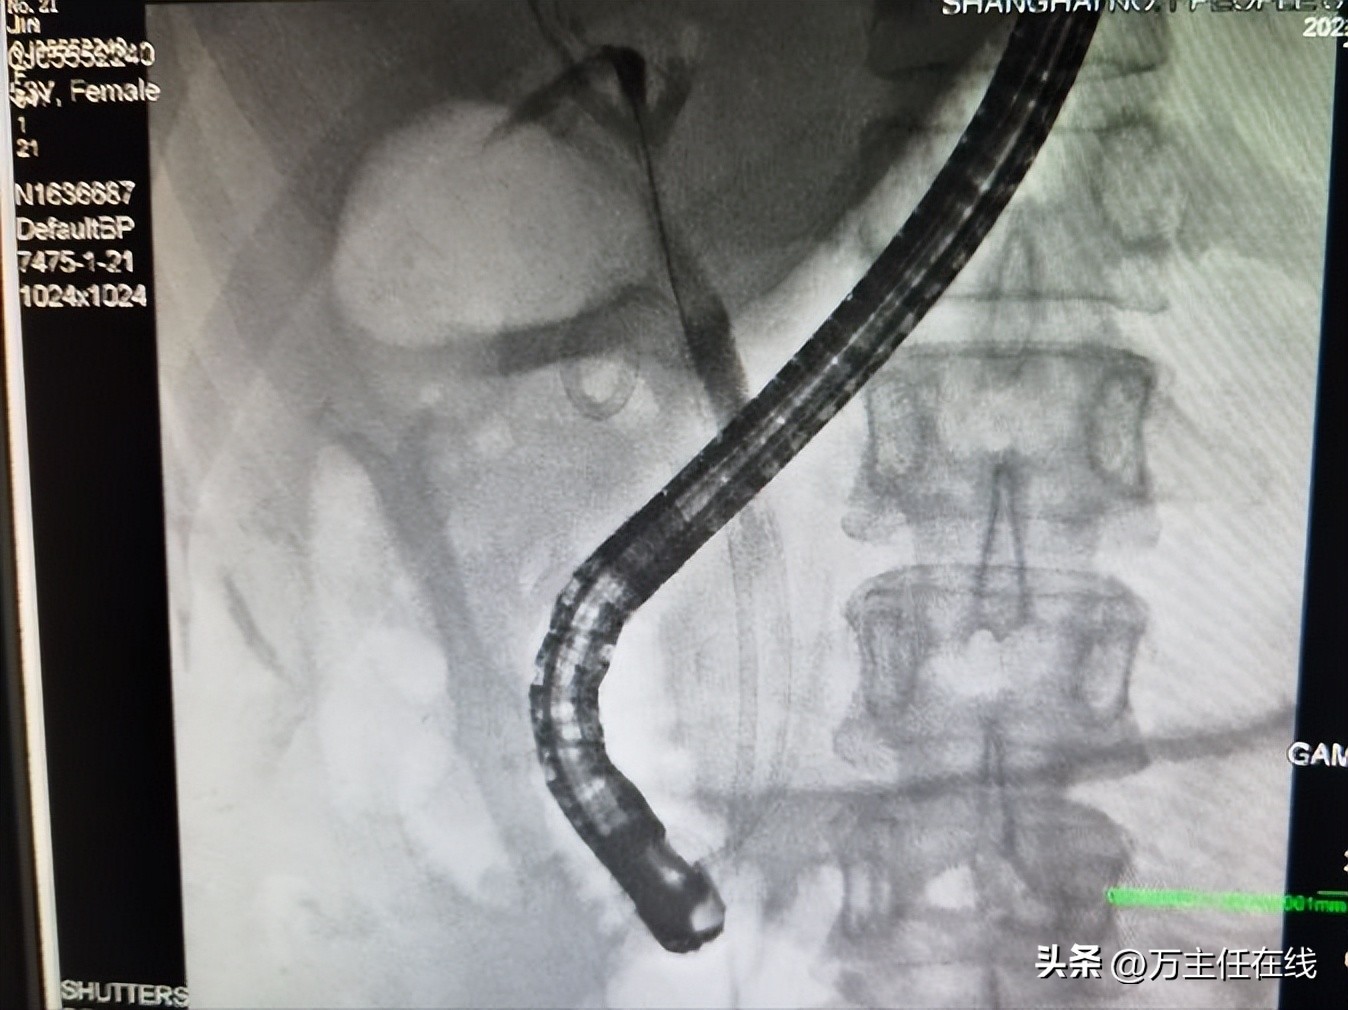

胆管、胰管及胆囊管支架置入后

胆道取石清理后,予胆管、胰管及胆囊管支架引流